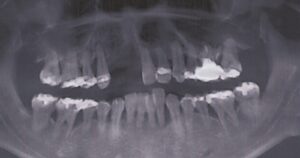

40歳・男性

初診日 2016. 12.  (5年経過症例)

1年前から他の歯科医院にて部分的な治療を受けたが、どんどん歯が悪くなって、見た目が良くない・噛めないとのことで再治療を希望された。昨日、上の前歯が自然に取れた、他の医院に行こうとしたところ知人に当医院を勧められ来院した。アングルクラスⅡであった。

治療法

全顎的に歯周病が進行し、ほとんどの歯に動揺が見られた。アングルクラスⅢで下顎前歯部に叢生が見られ、全顎の再生療法の後に、全顎的にオールセラミッククラウンを装着し、既存の被せのやり直しを行なった。

治療結果

審美的な仕上がりで、患者自身も満足した。5年経過し良好である。

現在は2〜3ヶ月おきのメインテナンス中である。

治療を行う上での 注意点 (リスク・副作用)

オールセラミックには欠け易いといったリスクがあるためナイトガードは必須である。